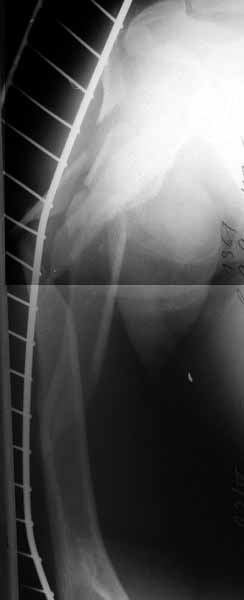

A male 35 y.o. was injured a week ago in a car accident. Admitted to us today with an acetabular fracture (ORIF required) and very comminuted open fractures of the humerus. The wound was debrided a week ago at the initial hospital and now looks calm. Image attached (sorry that only one view but another appeared to be almost the same). What would you do with th humerus?

That is the worst humerus I have seen. I think I would treat it nonoperative. There is a humerus rod with a blade plate that could be secured into the humeral head. Synthes make it. I have not used it.

Is the humeral head involved? If not, I would initially place in coaptation splint, and rex-ray. It may line up, in which case nonoperative treatment can be considered. Other options include locking nail, long bridge plate. IM nail preferred to those, but I am not sure we improve the natural history by operative treatment. Stiffness is expected, and in my experience, related to the original injury more than other factors.

It is very difficult to comment meaningfully without knowing whether or not the proximal humerus is involved and to what extent. There must be some sort of radiograph that shows the proximal humerus better.

Repair what I think is the Greater Tuberosity Fx, and then use small wire Ex Fix like Ilizarov . Mobile traction and preserve biologic integrity.

Alex The views you now show

demonstrate an extra articular fracture with good alignment on the AP, and some displacement on the lateral. This should be able to be managed with adjustment of the traction. Ilizarov is probably the best fixation if you decide to do so. However, it will heal with nonoperative treatment, with painless, reasonable function. Even if it does not heal primarily, the pieces will heal enough to become a single level problem, readily solved with compression plating.